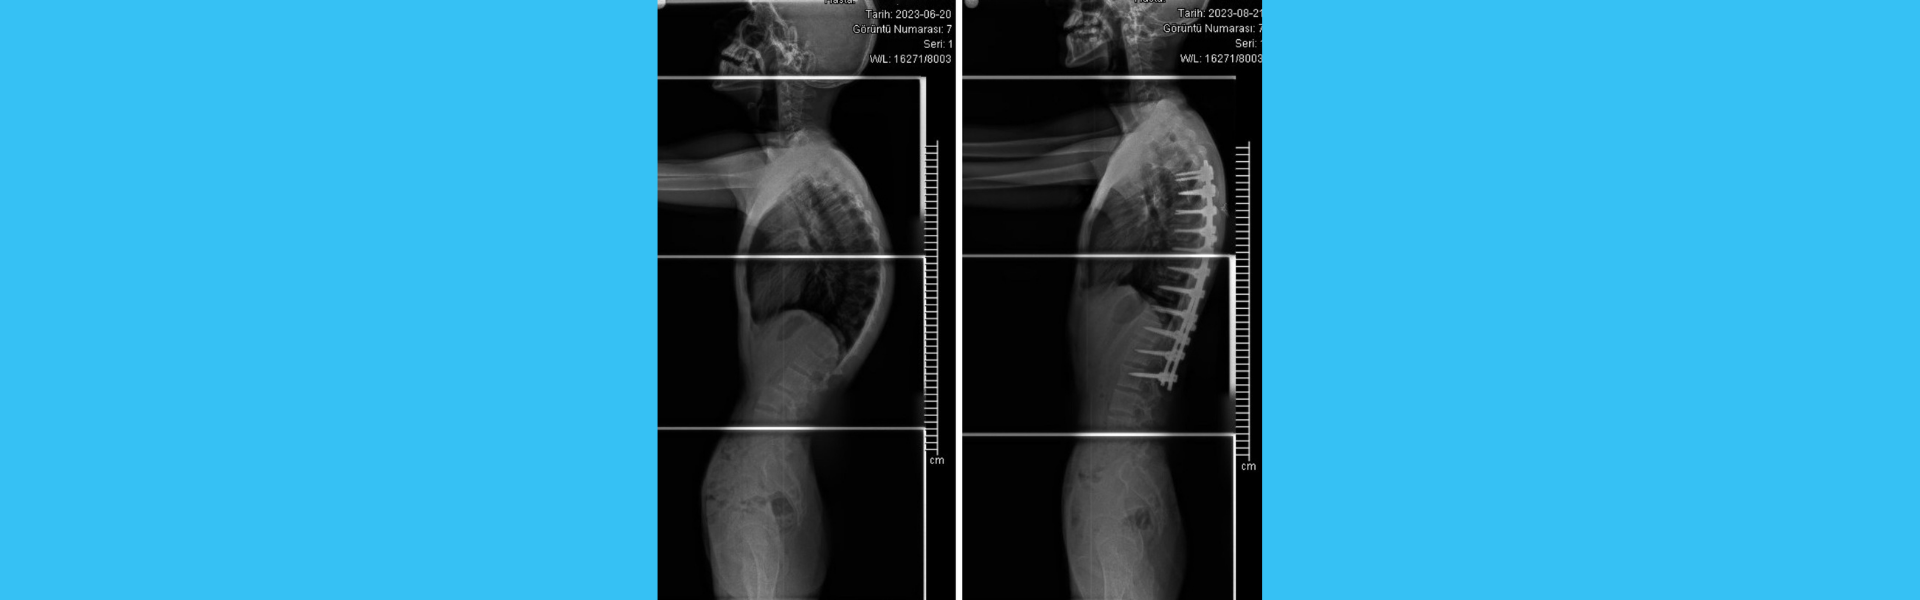

Lumbar Disc Herniation Surgery

Assoc. Prof. Dr. Adnan Demirci